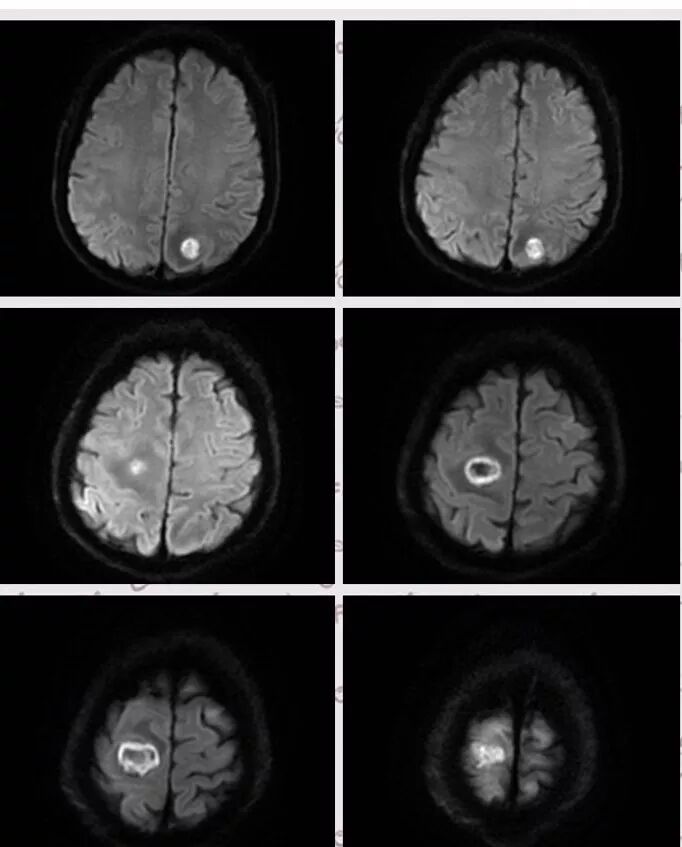

右肺下叶团块状密度增高影,边缘模糊,其内见液性低密度影,多发小气泡影及充气支气管征,考虑肺脓肿。颅内双侧顶叶长T2长T2病灶,周围水肿,DWI高信号,增强扫描囊壁环形强化,囊壁钙化,周围水肿,考虑脑脓肿。患者长期接触垃圾,什么菌都有,肺、脑脓肿,考虑肺克。再有肝脓肿就更支持了。

右肺下叶背段实变,广基底,糊墙,长轴与平行胸膜,周围有晕,支气管进入堵塞,可见低密度坏死及小空泡。颅内多发环形强化灶,符合脑脓肿三层结构,结合临床,考虑:感染性病变,隐球菌?鉴别肺克。

颅内多发类圆形等或长T1长T2信号,周围见少量环形水肿带,考虑多发脓肿,不符合转移瘤表现。综合肺脑脓肿,考虑隐球菌可能

右肺下叶见不规则软组织影,边缘不清,内夹杂气体,背段支气管未见明显阻断,增强扫描下叶病灶内见类圆形低强化区,其边缘光滑,见低强化区壁,颅脑左侧枕叶及双侧顶叶见多发长T1长T2信号,T2高信号内见类圆形异常信号,壁呈低信号,DWI环形壁未弥散受限,内容物弥散受限,周围为水肿区,增强扫描呈多发环形强化,考虑血源型感染,颅内及右肺下叶脓肿形成

脑内右侧顶叶病灶与其它脑内病灶不一致,壁弥散受限,内容物弥散低信号,转移瘤不能排除,其它脑内病灶支持脑脓肿

肺内病灶符合脓肿,颅内病灶几个表现不一样,多数脓腔弥散受限,壁不受限制,但有一个表现跟其他不同,内部不受限,壁弥散受限

多数薄壁,脓腔弥散受限是典型脑脓肿;右侧额叶的厚壁,壁受限,表现跟其他完全不一样,很是疑惑

颅内部分病灶是环形受限,中心没有受限,不支持脓肿

脑部病灶DWI受限,脓肿,中间也有受限,DWI第一,第二张图都是中间受限,第三,四是周围受限

今天这个颅脑病灶需要转移和脓肿鉴别,转移和脓肿都可以这样环形强化,但是脓肿是中心弥散受限,脓肿壁弥散不受限,转移和脓肿弥散正好相反,转移是环壁弥散受限,中心坏死区弥散不受限。

DWI值对鉴别脑脓肿与囊性脑转移瘤有重要意义。包膜期脑脓肿其内容物主要为炎症细胞、微生物及蛋白质,其黏稠度相对较高,水分子弥散受到限制,DWI表现为均匀高信号。转移瘤囊变区主要以浆液性坏死物为主,其黏稠度相对较低,水分子扩散速度相对较快,DWI表现为低信号

脑脓肿和囊性脑转移瘤的鉴别点就是粘液(结合水)浆液(自由水)的鉴别

下图是例举其他病例:

脑内多发结节,DWI壁弥散受限,腔不受限

颅内环形的高信号,但是可以发现这个的DWI环是厚的,但是增强扫描的环是非常薄的,如果是肿瘤的,就是壁的弥散受限是肿瘤细胞的话,那么他强化的环应该跟DWI的环的厚度是一样的,所以这个环形的低DWI高信号应该是脓肿。而且就是关于这个脓腔壁的,就是脓腔的外壁是非常模糊的,而内壁还是相对光整,环不是很完整。下面一个图,没有给到,DWI上可以看到沿着破溃的脓肿壁向外侵出去的感觉,如果是环形转移的,那么它的那个内壁是更加不光整,而外壁是相对比较清楚一些的。

这个颅内病灶增强扫描的无强化区范围与DWI高信号范围是一致的,所以还是脓腔内受限,至少时期不那么典型,不是纯粹的高信号,DWI是厚层、增强是薄层;而且扫描角度也不一样,所以无法完全对上

脓肿内的坏死、脓液形成也不是一次性完全形成的,就像在肝脓肿内,信号也是不一致的。重点还是在于强化区的地方弥散受限了还是无强化区的地方受限了,还是那句话,强化壁比弥散壁薄很多,无强化区比弥散不受限区范围大多了

3.脑内多发混杂信号病灶,显著长T1、显著长T2信号为主。注意TW1及TW2均显示环形等密度影(这在转移瘤是非常罕见的)且出现相应的环形强化。中央液化区DW扩散受限以及周边广泛水肿等,都符合典型多发脑脓肿改变。

4.脓腔较大,也更符合细菌感染。(脑内结核、隐球菌及奴卡菌感染病灶通常不易有如此大范围)